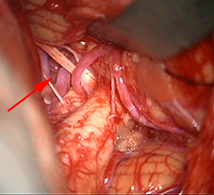

< 手術所見 >

左後下小脳動脈(矢印)は術後に本来の位置から移動している。